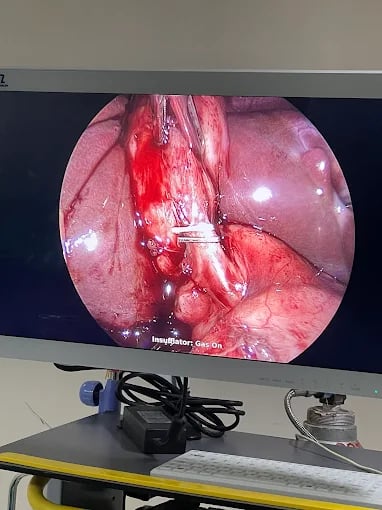

Laparoscopic surgery

Removal of Ovarian cyst

Gall Bladder removal by Lap